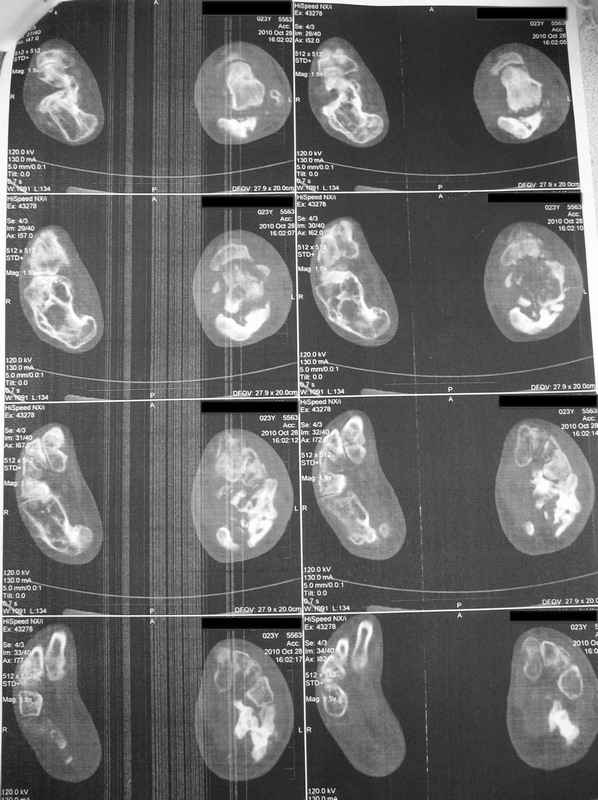

Молодая девушка со сросшимися многооскольчатыми переломами пяток и голеней.Young girl

with fractures of the calcaneus

Больная Н., 25 лет, падение с высоты (2008 г.). Жалобы на боли в области голеностопных

суставах, в области пяток при ходьбе. Лечилась в аппаратах внешней фиксации по поводу

открытых оскольчатых переломов обеих голеней, переломов пяток. Далее по поводу

несросшихся переломов голеней ЧКОС аппаратами внешней фиксации. Переломы срослись,

аппараты демонтированы весной 2010г. В левой пяточной области в месте проведения спицы

имеется сукровичное отделяемое. При ревизии гноя нет. Чем помочь девушке?

Patient N., age

25, falls from heights (2008). Complaints of pain in the ankles, in the heel when walking. She

was treated by external fixation on open comminuted fractures of both legs, fractures of the

calcaneus. Then she was treated by external fixation from nonunion of both legs. Now

fractures are fused, apparatuses removed in the spring of 2010. How to help a girl?